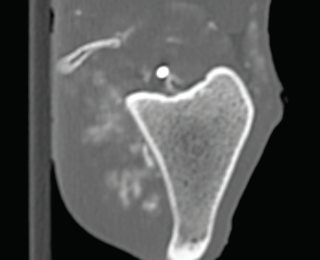

Proximity of the cranial tibial artery to the tibial bone at different angles of stifle extension in the dog: An ex vivo computed tomographic angiographic study

Cranial cruciate ligament disease (CCLD) is the most common cause of pelvic limb lameness in the dog. Tibial plateau levelling osteotomy (TPLO) is one of the most commonly performed procedures to treat CCLD by neutralising cranial tibial thrust and providing dynamic stability to the stifle joint at a standing angle. Excessive haemorrhage during the TPLO procedure has been described as an infrequent but potentially severe intraoperative complication, with a reported incidence of up to 1.6%. Damage to the proximal tibial musculature, cranial tibial artery or its five-way vascular network, or the cranial tibial vein during muscle elevation or performance of the osteotomy has been implicated as the cause of this excessive haemorrhage.1-6 In one study, the authors recommended performing the osteotomy with the stifle in flexion to allow the gastrocnemius muscle to relax and the cranial tibial artery to move caudally, potentially decreasing the risk of injury to the vessel during performance of the osteotomy. However, there have been no studies investigating the proximity of the cranial tibial artery to the tibial bone at different angles of stifle extension in dogs with intact or deficient cranial cruciate ligament. Therefore, the objectives of this study led by Dr Mullins are to: determine the shortest distance between the cranial tibial artery and the tibial bone at different angles of stifle extension in canine cadaveric stifles with an intact CCL and a completely transected CCL; and to investigate whether complete surgical transection of the CCL would result in a significant change in the distance between the cranial tibial artery and the tibial bone at any angle of stifle extension.